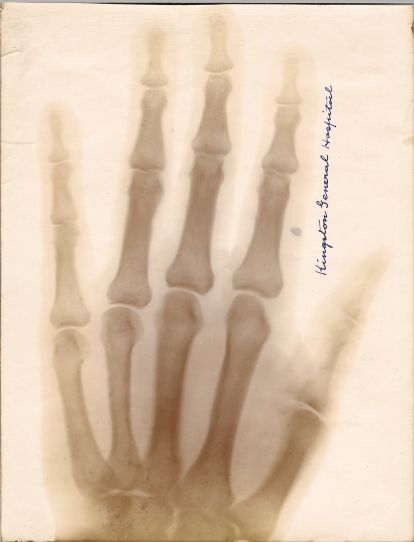

The arrival of X-ray technology -

X-rays first made their appearance in Kingston on February 17, 1896, when the Weekly Whig reported that Captain John Bray Cochrane (1860-1946), Professor of Physics...

X-ray